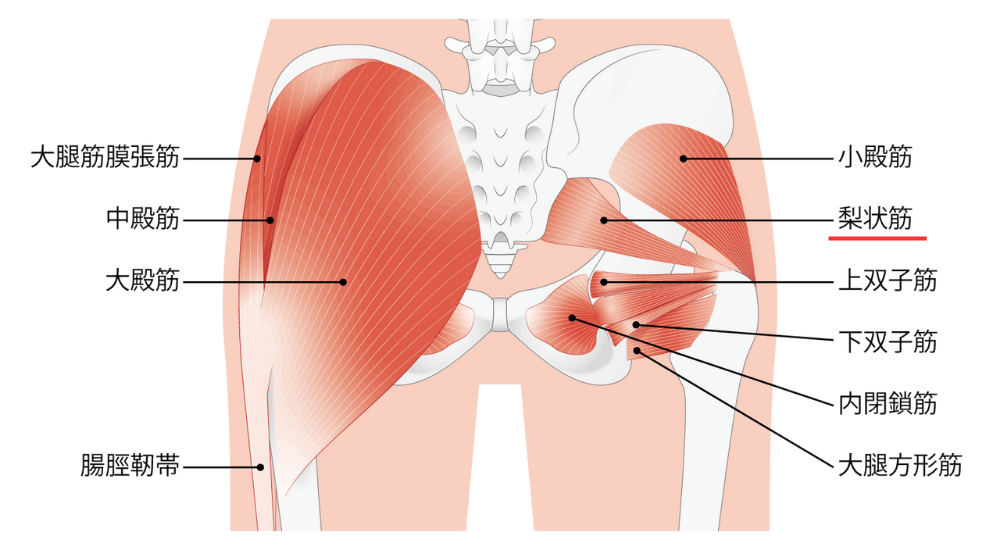

- 大臀筋・中臀筋・梨状筋:

お尻の筋肉。股関節の動きや骨盤の安定に重要で、機能低下や硬さが腰に影響することがある。梨状筋が硬くなると、坐骨神経を圧迫し、腰やお尻、足にかけての痛みを引き起こすことがあります。(梨状筋症候群)